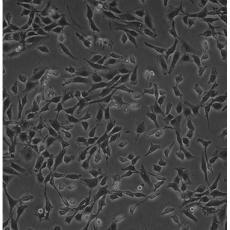

STO

產品名稱 STO

中文名稱 小鼠胚成纖維細胞

組織來源 胚胎;成纖維細胞;SIM

生長特性 adherent

培養基 DMEM+10% FBS+1% P/S

形態特征 epithelial

細胞描述 STO是一株繼代生長的胚成纖維細胞系,可用于制備飼養層細胞(feederlayers)和其他研究。

細胞傳代步驟 如果細胞密度達80%-90%,即可進行傳代培養。1. 棄去培養上清,用不含鈣、鎂離子的PBS潤洗細胞1-2次。2. 加2ml消化液(0.25%Trypsin-0.53mM EDTA)于培養瓶中,置于37℃培養箱中消化1-2分鐘,然后在顯微鏡下觀察細胞消化情況,若細胞大部分變圓并脫落,迅速拿回操作臺,輕敲幾下培養瓶后加少量培養基終止消化。3. 按6-8ml/瓶補加培養基,輕輕打勻后吸出,在1000RPM條件下離心4分鐘,棄去上清液,補加1-2mL培養液后吹勻。4. 將細胞懸液按1:2到1:5的比例分到新的含8ml培養基的新皿中或者瓶中

復蘇細胞步驟 將含有1mL細胞懸液的凍存管在37℃水浴中迅速搖晃解凍,加入4mL培養基混合均勻。在1000RPM條件下離心4分鐘,棄去上清液,補加1-2mL培養基后吹勻。然后將所有細胞懸液加入培養瓶中培養過夜(或將細胞懸液加入10cm皿中,加入約8ml培養基,培養過夜)。第二天換液并檢查細胞密度。

細胞凍存步驟 :待細胞生長狀態良好時,可進行細胞凍存。下面T25瓶為例;1.細胞凍存時,棄去培養基后,PBS清洗瓶底1-2次后加入1ml胰酶,細胞變圓脫落后,加入2ml完全培養基終止消化,可使用血球計數板計數。2.1000RPM離心5分鐘去掉上清。用血清重懸浮,加DMSO至最終濃度為10%。加入DMSO后迅速混勻,按每1ml的數量分配到凍存管中,注意凍存管做好標識。本公司按每個凍存管細胞數目大于1X106個細胞凍存。3.將凍存管置于程序降溫盒中,放入-80度冰箱,至少2個小時以后轉入液氮灌儲存。記錄凍存管位置以便下次拿取。

細胞凍存 Freeze medium: 50% basal medium+40% FBS+10%.DMSOStorage temperature: liquid nitrogen vapor phase

細胞運輸 干冰運輸(2ml凍存管)或活細胞運輸(T25細胞瓶)